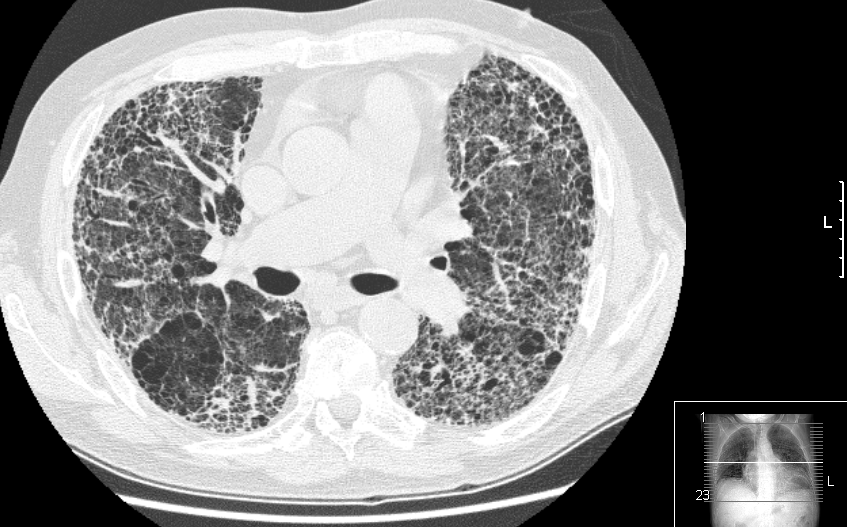

IPF 是一种罕见、严重且不断进展的疾病,目前尚无治愈方法。当肺部气囊(肺泡)周围的肺组织变得厚实僵硬时,就会发生 IPF。随着时间推移,这些变化会导致永久性肺部瘢痕(纤维化),使呼吸变得更加困难。该病主要影响 50 岁以上人群,男性患病率高于女性,最常见的诊断年龄为 60 至 70 岁。

IPF 的致死率高于多种常见癌症。数据显示,IPF 患者的五年生存率低于前列腺癌、女性乳腺癌和结肠癌。约半数患者在确诊后五年内死亡。许多 IPF 患者还会经历急性加重期,即症状突然加剧的时期。典型症状包括干咳、持续咳嗽、呼吸困难、疲劳和杵状指(指尖变宽变圆)。